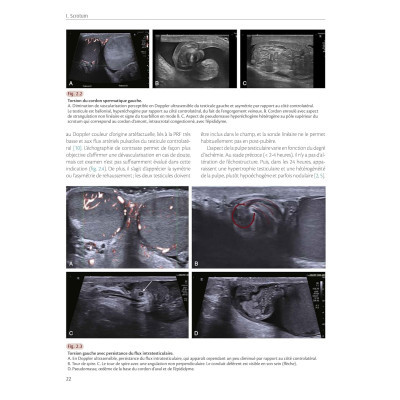

Les motifs de consultation et les types d'atteintes sont nombreux. Ce nouveau volume de la collection des ' Syllabus de la SFR ' (Société Française de Radiologie) et de la SIGU (Société d'Imagerie Génito-Urinaire) décrit de façon exhaustive ces affections, qu'elles concernent le scrotum, la verge ou la prostate. C'est ainsi un état de l'art de l'Imagerie de l'appareil génital et reproducteur masculin qui est proposé. Des connaissances anatomiques et physiopathologiques détaillées sont apportées afin d'affiner toujours plus l'interprétation des examens et d'envisager les options thérapeutiques. La Traumatologie , les atteintes cancéreuses, les pathologies courantes et plus rares font l'objet de chapitres spécifiques, de même que le bilan de l'infertilité. Les différentes techniques d'acquisition en échographie, en écho-Doppler et en IRM sont aussi abordées, sans oublier la Radiologie interventionnelle.

Richement illustré et complet, présenté de façon didactique et rédigé par les meilleurs experts en Imagerie du pelvis masculin, cet ouvrage constitue la référence actuelle sur le sujet. Il est incontournable pour tous les radiologues en formation ou plus expérimentés devant mener à bien des examens d'Imagerie chez l'homme, mais également pour les urologues désireux de mieux comprendre l'Imagerie de cette région.

- 400 illustrations de grande qualité.